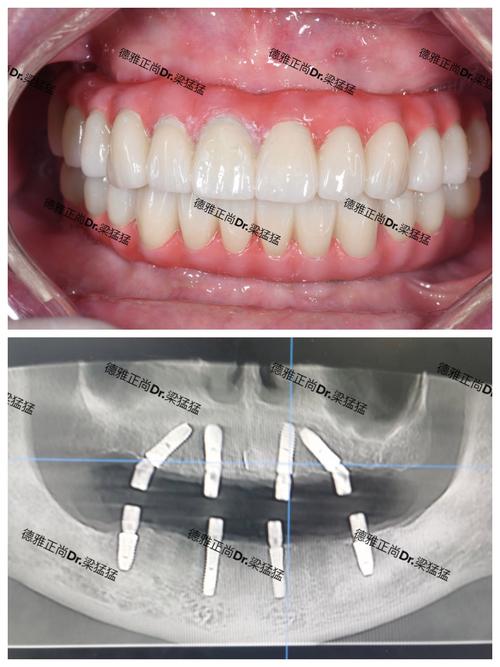

(图片来源网络,侵删)- 查看案例: 要求查看该医生或机构与你情况相似(如骨条件、缺牙位置、年龄等)的成功案例,观察其修复效果(尤其是美观和功能)。